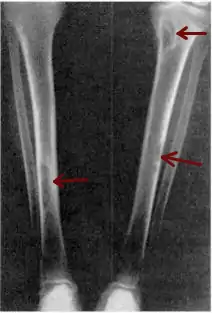

| Osteitis fibrosa cystica of the tibia. Arrows point to the brown tumors which are typically present in bones of people with OFC. | |